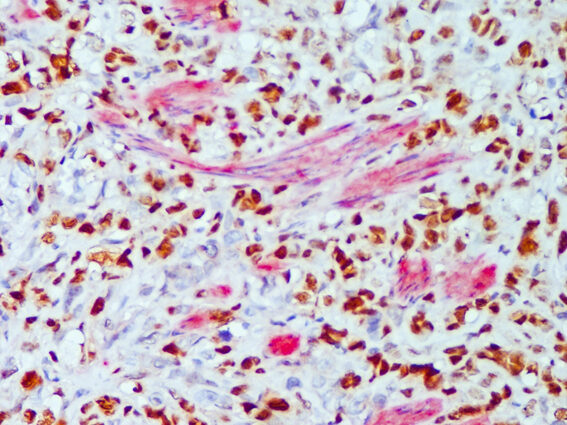

- La importancia de estudiar esta patología radica en que es el tipo de cáncer que causa más muertes en mujeres en la mayor parte de los países. Si bien existen terapias muy efectivas, muchas veces la paciente presenta resistencia a la terapia indicada o bien el diagnóstico se realiza cuando el cáncer ya está avanzado. Enfocarse en el estudio del cáncer de mama ha permitido en los últimos años lograr avances importantes para el tratamiento de esta enfermedad.

- El laboratorio posee dos líneas de investigación fundamentales. Una de ellas implica el efecto de las hormonas del estrés en la evolución del cáncer de mama en modelos experimentales. La segunda línea de investigación es el estudio y comprensión de los mecanismos involucrados en la resistencia a la terapia hormonal, utilizada en los tumores más frecuentes.

- Nuestros objetivos implican mejorar los tratamientos ya existentes para las pacientes con cáncer de mama, especialmente para aquellos casos avanzados o que muestran resistencia a las terapias utilizadas actualmente. Comprender los mecanismos involucrados en estos casos puede sugerir alternativas terapéuticas que complementen o mejoren las terapias existentes.